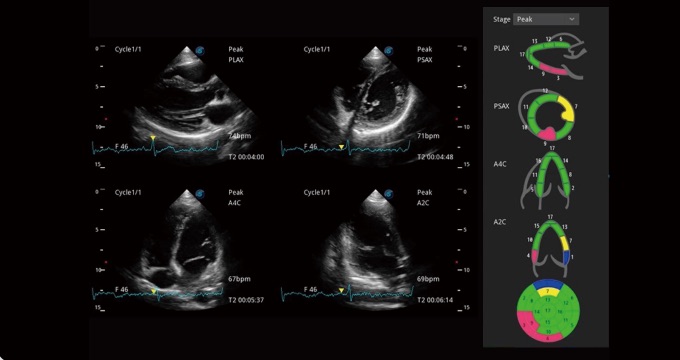

支持運(yùn)動(dòng)和藥物負(fù)荷協(xié)議、多心動(dòng)周期存儲(chǔ)選擇,為臨床觀察心肌負(fù)荷狀態(tài)下的室壁節(jié)段運(yùn)動(dòng)、評(píng)估心肌缺血狀態(tài)提供更多的解決方案。

通過(guò)心肌識(shí)別技術(shù)和二維斑點(diǎn)追蹤技術(shù)相結(jié)合,計(jì)算心肌各節(jié)段的應(yīng)變應(yīng)變率、速度、位移并以曲線圖顯示,實(shí)現(xiàn)整體或者局部心肌定量分析。同時(shí)可呈現(xiàn)牛眼圖直觀和準(zhǔn)確診斷心肌的運(yùn)動(dòng)情況。